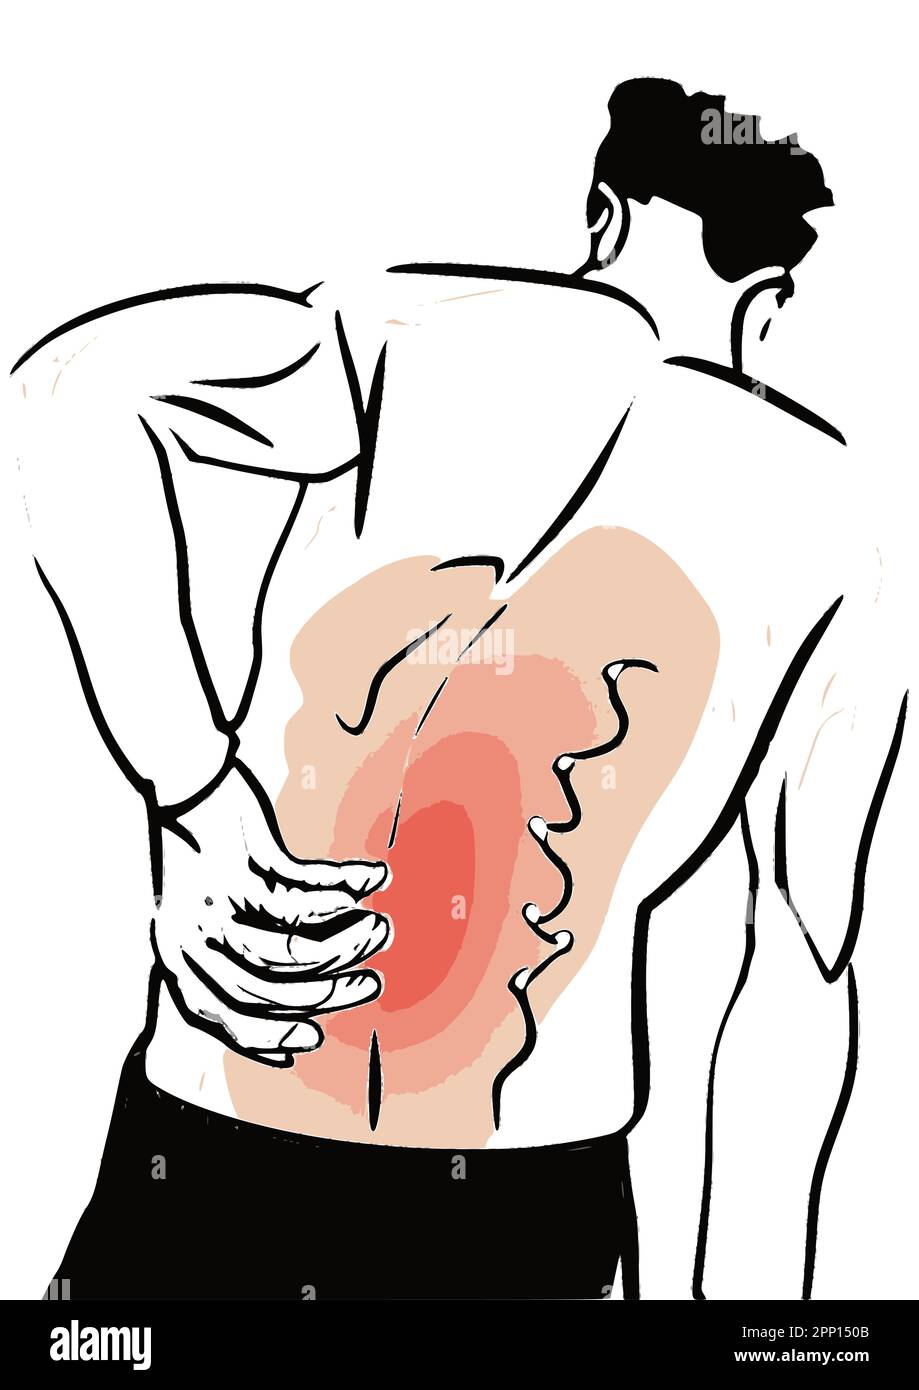

Homme souffrant de douleurs soudaines de dos, touchant le bas du dos, bas du dos image vecteur d'inflammation. Illustration de Vecteurhttps://www.alamyimages.fr/image-license-details/?v=1https://www.alamyimages.fr/homme-souffrant-de-douleurs-soudaines-de-dos-touchant-le-bas-du-dos-bas-du-dos-image-vecteur-d-inflammation-image547069723.html

Homme souffrant de douleurs soudaines de dos, touchant le bas du dos, bas du dos image vecteur d'inflammation. Illustration de Vecteurhttps://www.alamyimages.fr/image-license-details/?v=1https://www.alamyimages.fr/homme-souffrant-de-douleurs-soudaines-de-dos-touchant-le-bas-du-dos-bas-du-dos-image-vecteur-d-inflammation-image547069723.htmlRF2PP150B–Homme souffrant de douleurs soudaines de dos, touchant le bas du dos, bas du dos image vecteur d'inflammation.